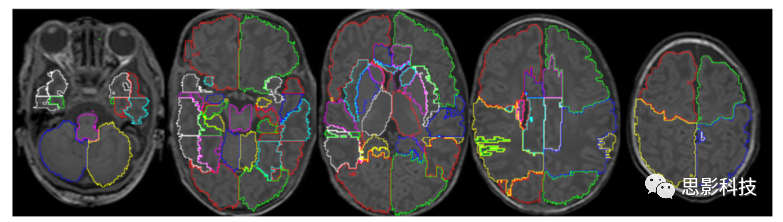

現(xiàn)有文獻(xiàn)中為圍產(chǎn)期大腦構(gòu)建的個體圖譜有限。Oishi等人(2011)構(gòu)建了一個由T1、T2DTI組成的多模態(tài)新生兒腦圖譜,并在單個被試腦圖像上手工劃分了122個區(qū)域。手工劃分是基于DTI數(shù)據(jù)上觀察到的白質(zhì)束和回旋模式。相反,Gousias等人根據(jù)T1T2數(shù)據(jù)生成了多個個體圖譜。他們在大約足月年齡的不同掃描時間的20名新生兒上手工描繪了50個結(jié)構(gòu)(Gousias等人(2012)的一個圖譜如圖5所示)de Macedo Rodrigues等人(2015)使用T1圖像構(gòu)建了不同年齡的多個個體圖譜。將23例掃描年齡在02歲之間的嬰兒(包括4名新生兒)的腦部MR圖像手動分割為32個區(qū)域。Alexander等人(2016年)建立了最新的腦圖譜,在10例足月新生兒的T2圖像中描繪了100個區(qū)域。該圖譜的一個重要特征是它復(fù)制了Desikan-Killiany方案,該方案在成人研究中廣泛使用并用于新生兒大腦(見圖6)。

Gousias等人(2012)手動描繪的圖譜將大腦分為50個區(qū)域。